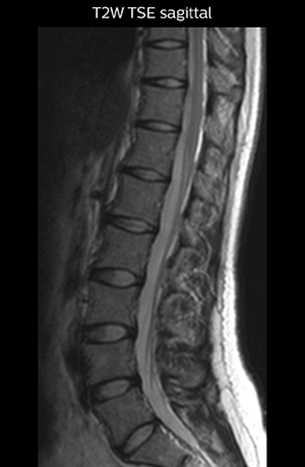

“For example, in sagittal images, when the presence of fat is observed in the intervertebral foramen, it suggests that there is a margin around the nerve. Similarly, the absence of fat indicates that the nerve is being compressed. So, we used to deduce nerve compression indirectly. With NerveVIEW, however, we can observe the condition of the nerves directly, regardless of the presence or absence of fat. We always prefer such direct observation of anatomy over having to make an inference about it.”

“NerveVIEW is really useful for those cases where a nerve disorder is strongly suspected based on the clinical examination but our regular MRI images do not show any findings. These atypical herniations and spinal canal stenosis, occurring in 5% to 15% of the total lumbar herniation/stenosis cases are our main target when using NerveVIEW,” says Dr. Yabuki.

“The intra-luminal signal of veins, especially around the intervertebral space, can be suppressed well with NerveVIEW. As a result, we can easily observe the detailed nerve structure around the posterior ganglion,” he says. “This is why we use 3D NerveVIEW for intraforaminal stenosis and extraforaminal stenosis/herniation (lateral disc herniation). On the other hand, if herniation is suspected to exist inside the dorsal root ganglion (DRG), balanced TFE or ProSet-FFE is applied. NerveVIEW is not suitable for evaluating the median type of herniation.” The SE-EPI DWI-based method for MR neurography works well for large FOV exams like whole-body MRI, but focal examination of nerves is often limited by the attainable spatial resolution (both inplane and slice direction) and geometric distortion. “3D NerveVIEW achieves higher in-plane resolution – close to our other routine spine sequences – and the source images can be used instead of adding a fat-suppressed T2-weighted sequence,” Tanji says.